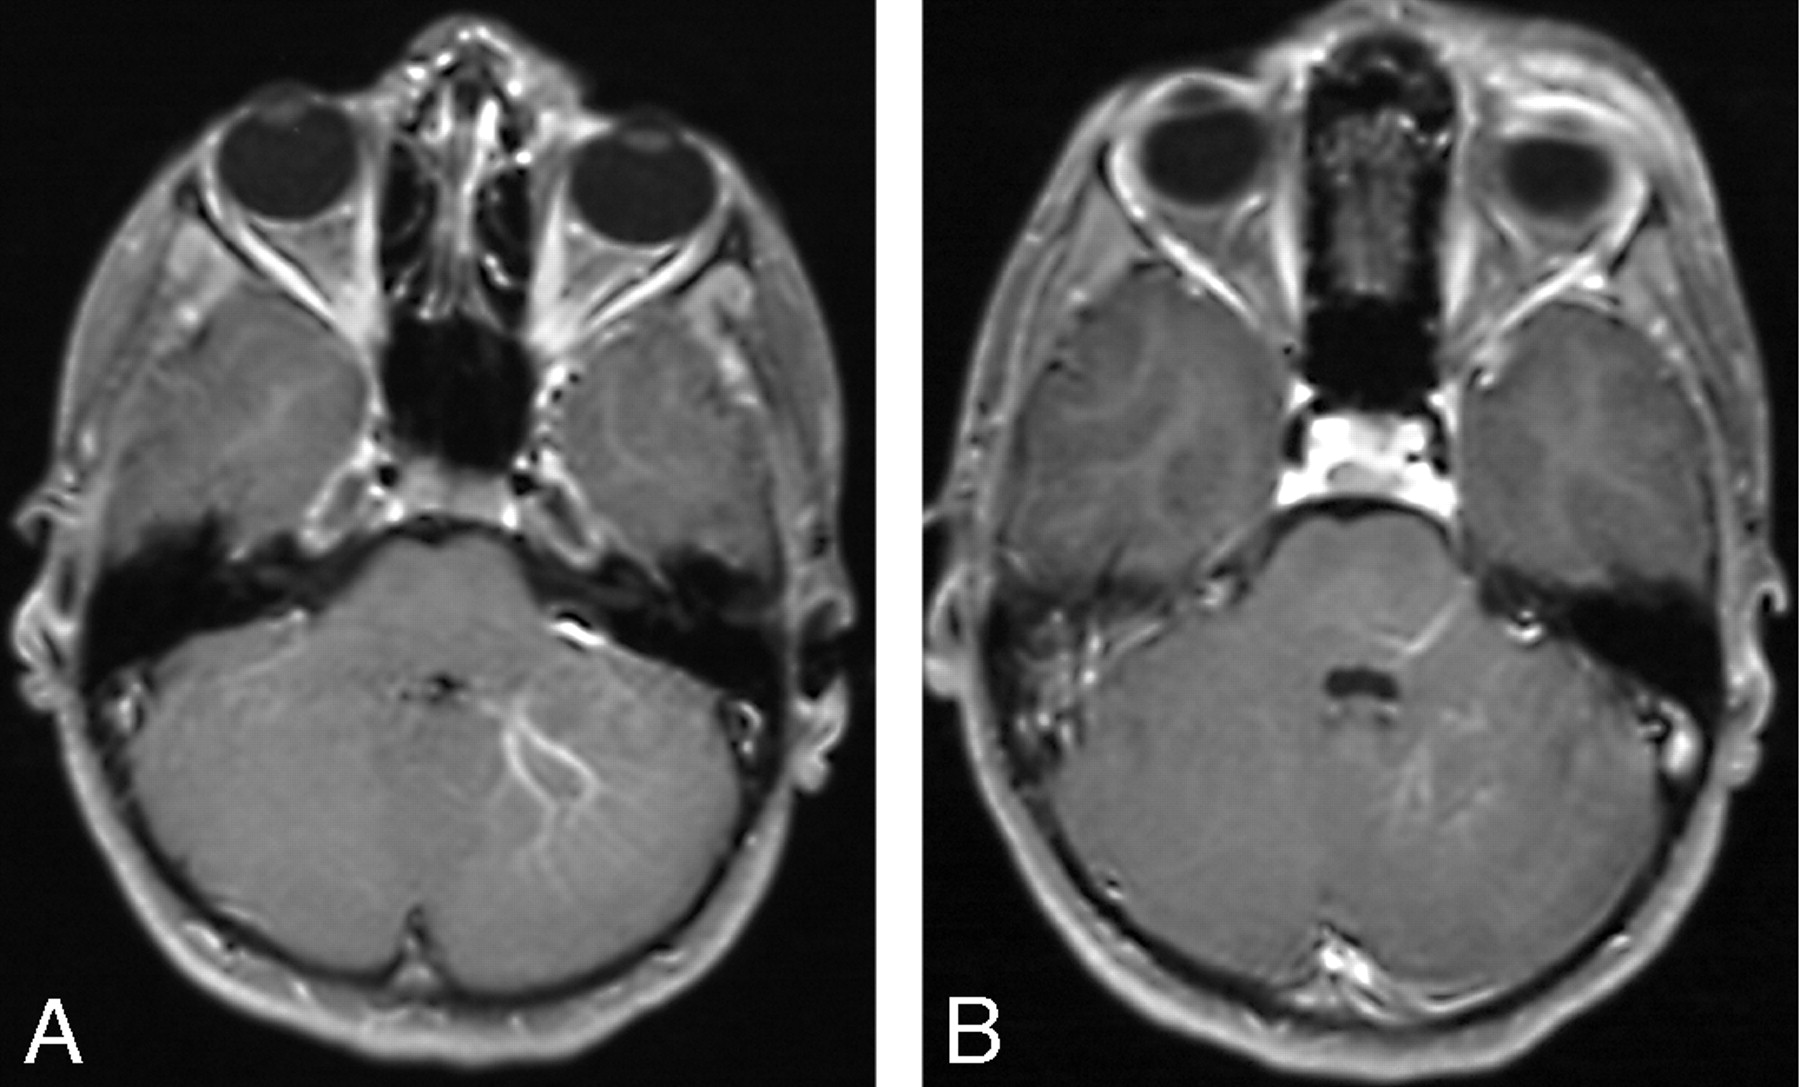

A and B, Right orbital/periorbital lymphatic malformation with right posterior dural AVM.

A, Axial T2-weighted image shows the orbital and periorbital low-flow vascular malformation as dilation of the right transverse sinus which has flow voids in its wall. Associated right hemispheric atrophy is indicated by dilation of the temporal horn of the right lateral ventricle.

B, Gradient recalled-echo sequence confirms the high-flow nature of this dural sinus lesion.